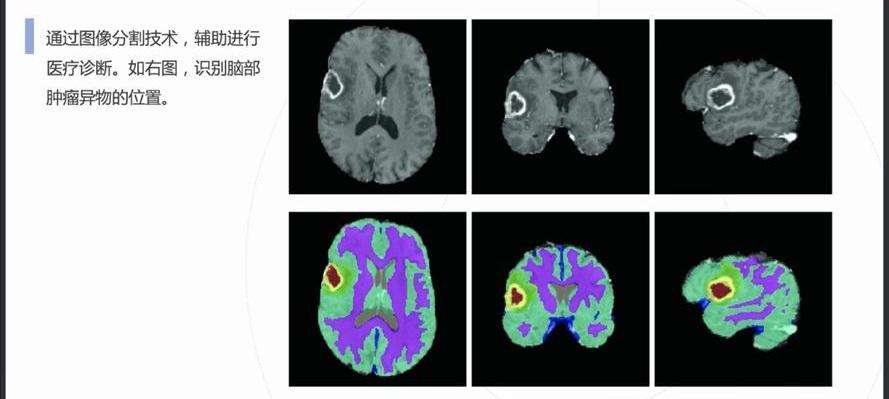

自動病灶檢測:借助計算機(jī)視覺和人工智能算法,CCD視覺檢測設(shè)備能夠自動識別醫(yī)學(xué)影像中的病灶區(qū)域,如腫瘤、炎癥、骨折等異常結(jié)構(gòu)。

早期癌癥篩查:在乳腺癌、肺癌、皮膚癌等癌癥的早期篩查中,CCD視覺檢測系統(tǒng)通過分析X光、MRI或CT掃描圖像,識別出腫瘤的早期跡象,顯著提高早期診斷率。